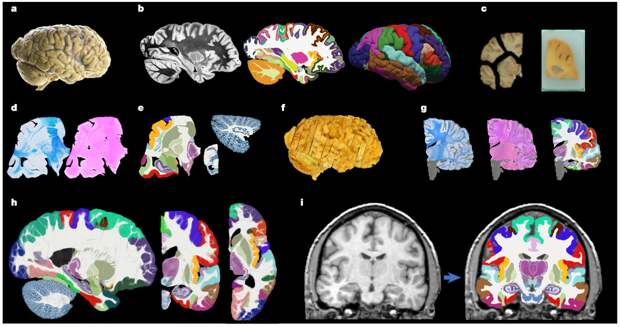

Этапы работы в NextBrain. На снимке — автоматизированная сегментация сканирования in vivo на 333 области интереса с использованием атласа NextBrain. Credit: Casamitjana A. et al. / Nature 2025

Исследователи взяли полушария мозга пяти посмертных доноров, подготовили тысячи гистологических срезов, которые окрасили специальными красителями, отражающими разный клеточный состав мозговых структур. С помощью искусственного интеллекта они собрали эти тысячи плоских «картинок» обратно в единую трехмерную модель, убрав все искажения, возникшие при нарезке.

В результате удалось получить инструмент NextBrain, который позволяет анализировать разные участки мозга, причем делает это с определенной вероятностью, что отражает реальную, «размытую» природу границ в биологических тканях, и чего ранее существовавшие инструменты не позволяли делать. Ранее известный атлас MNI позволял выделять только 138 областей интереса.

Кроме того, ученые создали и выложили в открытый доступ не только сам атлас, но и все исходные данные, а также инструмент для автоматической сегментации. Теперь любой исследователь, загрузив стандартный МРТ-снимок, может всего за полчаса получить его детализированную разметку на все 333 области интереса.